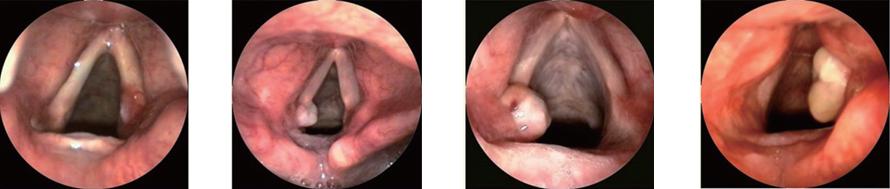

肉芽肿的Farwell分度

I度:局限在声带突上固定的、无溃疡的肉芽肿

II度:局限并突出于声带突或有溃疡面的肉芽肿

III度:声带充分外展时肉芽肿内界超出声带突但未超过气道中线

IV度:声带充分外展时肉芽肿内界超过声带中线

I度 II度 III度 IV 度